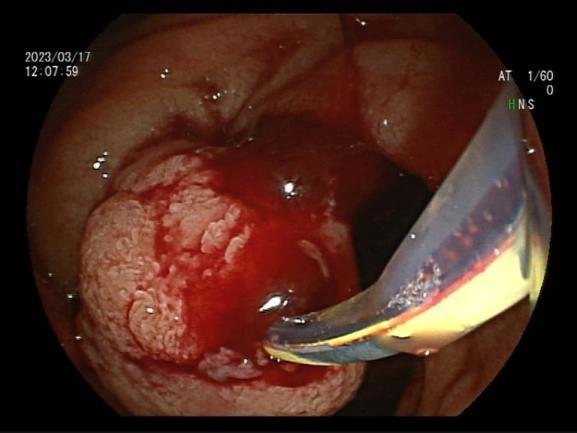

三、早期消化道肿瘤ESD技术

内镜下粘膜剥离术(ESD),具有超级微创、安全性高、住院时间短及费用低等优势。

直肠巨大绒毛状腺瘤 内镜下粘膜剥离过程

粘膜剥离术后创面 剥离的巨大腺瘤